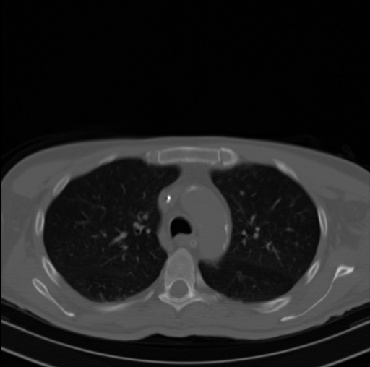

Early and reliable COVID-19 diagnosis based on chest 3-D CT scans can assist medical specialists in vital circumstances. Deep learning methodologies constitute a main approach for chest CT scan analysis and disease prediction. However, large annotated databases are necessary for developing deep learning models that are able to provide COVID-19 diagnosis across various medical environments in different countries. Due to privacy issues, publicly available COVID-19 CT datasets are highly difficult to obtain, which hinders the research and development of AI-enabled diagnosis methods of COVID-19 based on CT scans. In this paper we present the COV19-CT-DB database which is annotated for COVID-19, consisting of about 5,000 3-D CT scans, We have split the database in training, validation and test datasets. The former two datasets can be used for training and validation of machine learning models, while the latter will be used for evaluation of the developed models. We also present a deep learning approach, based on a CNN-RNN network and report its performance on the COVID19-CT-DB database.